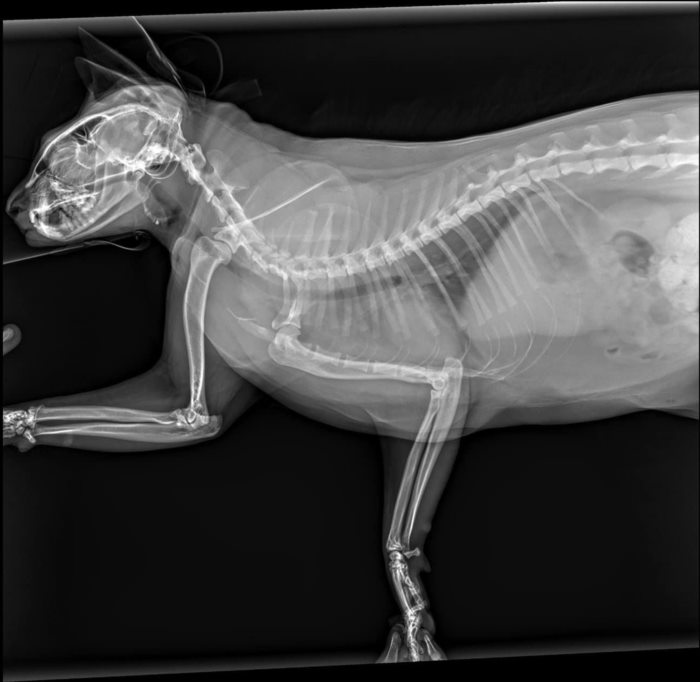

โดยอาการบาดเจ็บที่มักพบจากการที่แมวตกจากที่สูง ได้แก่ กระดูกหัก ส่วนใหญ่มักเป็นกระดูกขากรรไกร เพราะคางแมวกระแทกกับพื้นตอนที่ตกลงมา กรณีที่พบบ่อยที่สุดคือ กระดูกขากรรไกรหักและฟันร้าว นอกจากนี้ยังพบอาการบาดเจ็บที่ขา ภาวะบาดเจ็บที่ข้อต่อ เส้นเอ็นฉีกขาด หรือขาหัก อาการบาดเจ็บภายใน โดยเฉพาะที่ปอด เป็นต้น ทำให้บรรดาเจ้าของแมวต้องปรับปรุงห้องพักที่อยู่ตามตึกสูงให้มีความปลอดภัยสำหรับสัตว์เลี้ยงมากขึ้น

สาเหตุที่แมวตกจากตึกสูงไม่เกิน 7 ชั้นมีโอกาสบาดเจ็บขาหัก หรือบาดเจ็บมากกว่าตกจากที่สูงกว่านั้น เพราะกรณีตกจากที่สูง แมวจะมีสัญชาตญาณให้มันกางขาทั้งสี่ขาออก (เหมือนนักกระโดดร่มที่กางแขนขา) ส่งผลให้เพิ่มแรงต้านอากาศ ความเร็วขณะที่แมวร่วงจะช้าลง ขณะที่มันก็จะเตรียมตัวลงสู่พื้นแบบกระจายแรงกระแทกไปให้ทั่วร่างกายอันยืดหยุ่นของมัน และเนื่องจากมันมีน้ำหนักตัวค่อนข้างน้อย จึงไม่ทำให้แมวตาย แต่ถ้าแมวตกจากตึกเตี้ย ๆ ด้วยระยะทางที่สั้นเกินไปมันกลับไม่สามารถเปลี่ยนท่ากลางอากาศได้ทัน ร่างกายจึงกระแทกกับพื้นได้